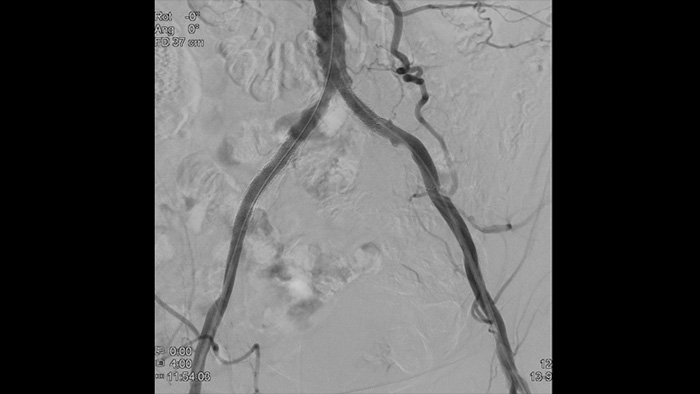

Für einen effektiven Zugang zum arteriellen System ist eine realistische Visualisierung des arteriellen Gefässsystems erforderlich. Unser integriertes CX50-Ultraschallsystem liefert hochwertige Bilder der Radialarterie und -venen, um radiale Zugangsinterventionen zu unterstützen.